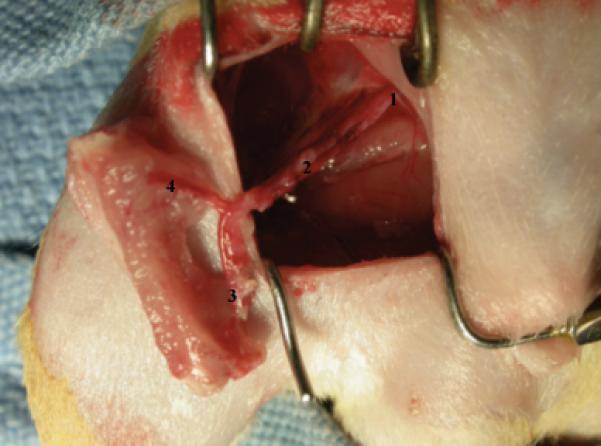

Figure 1.

Allograft in place after anastomoses in the recipient rat vessels: (1) Common iliac vessels, (2) Lateral femoral circumflex vessels, (3) Distal nutrient branch to femur, (4) Femoral vessels with proximal nutrient branch.